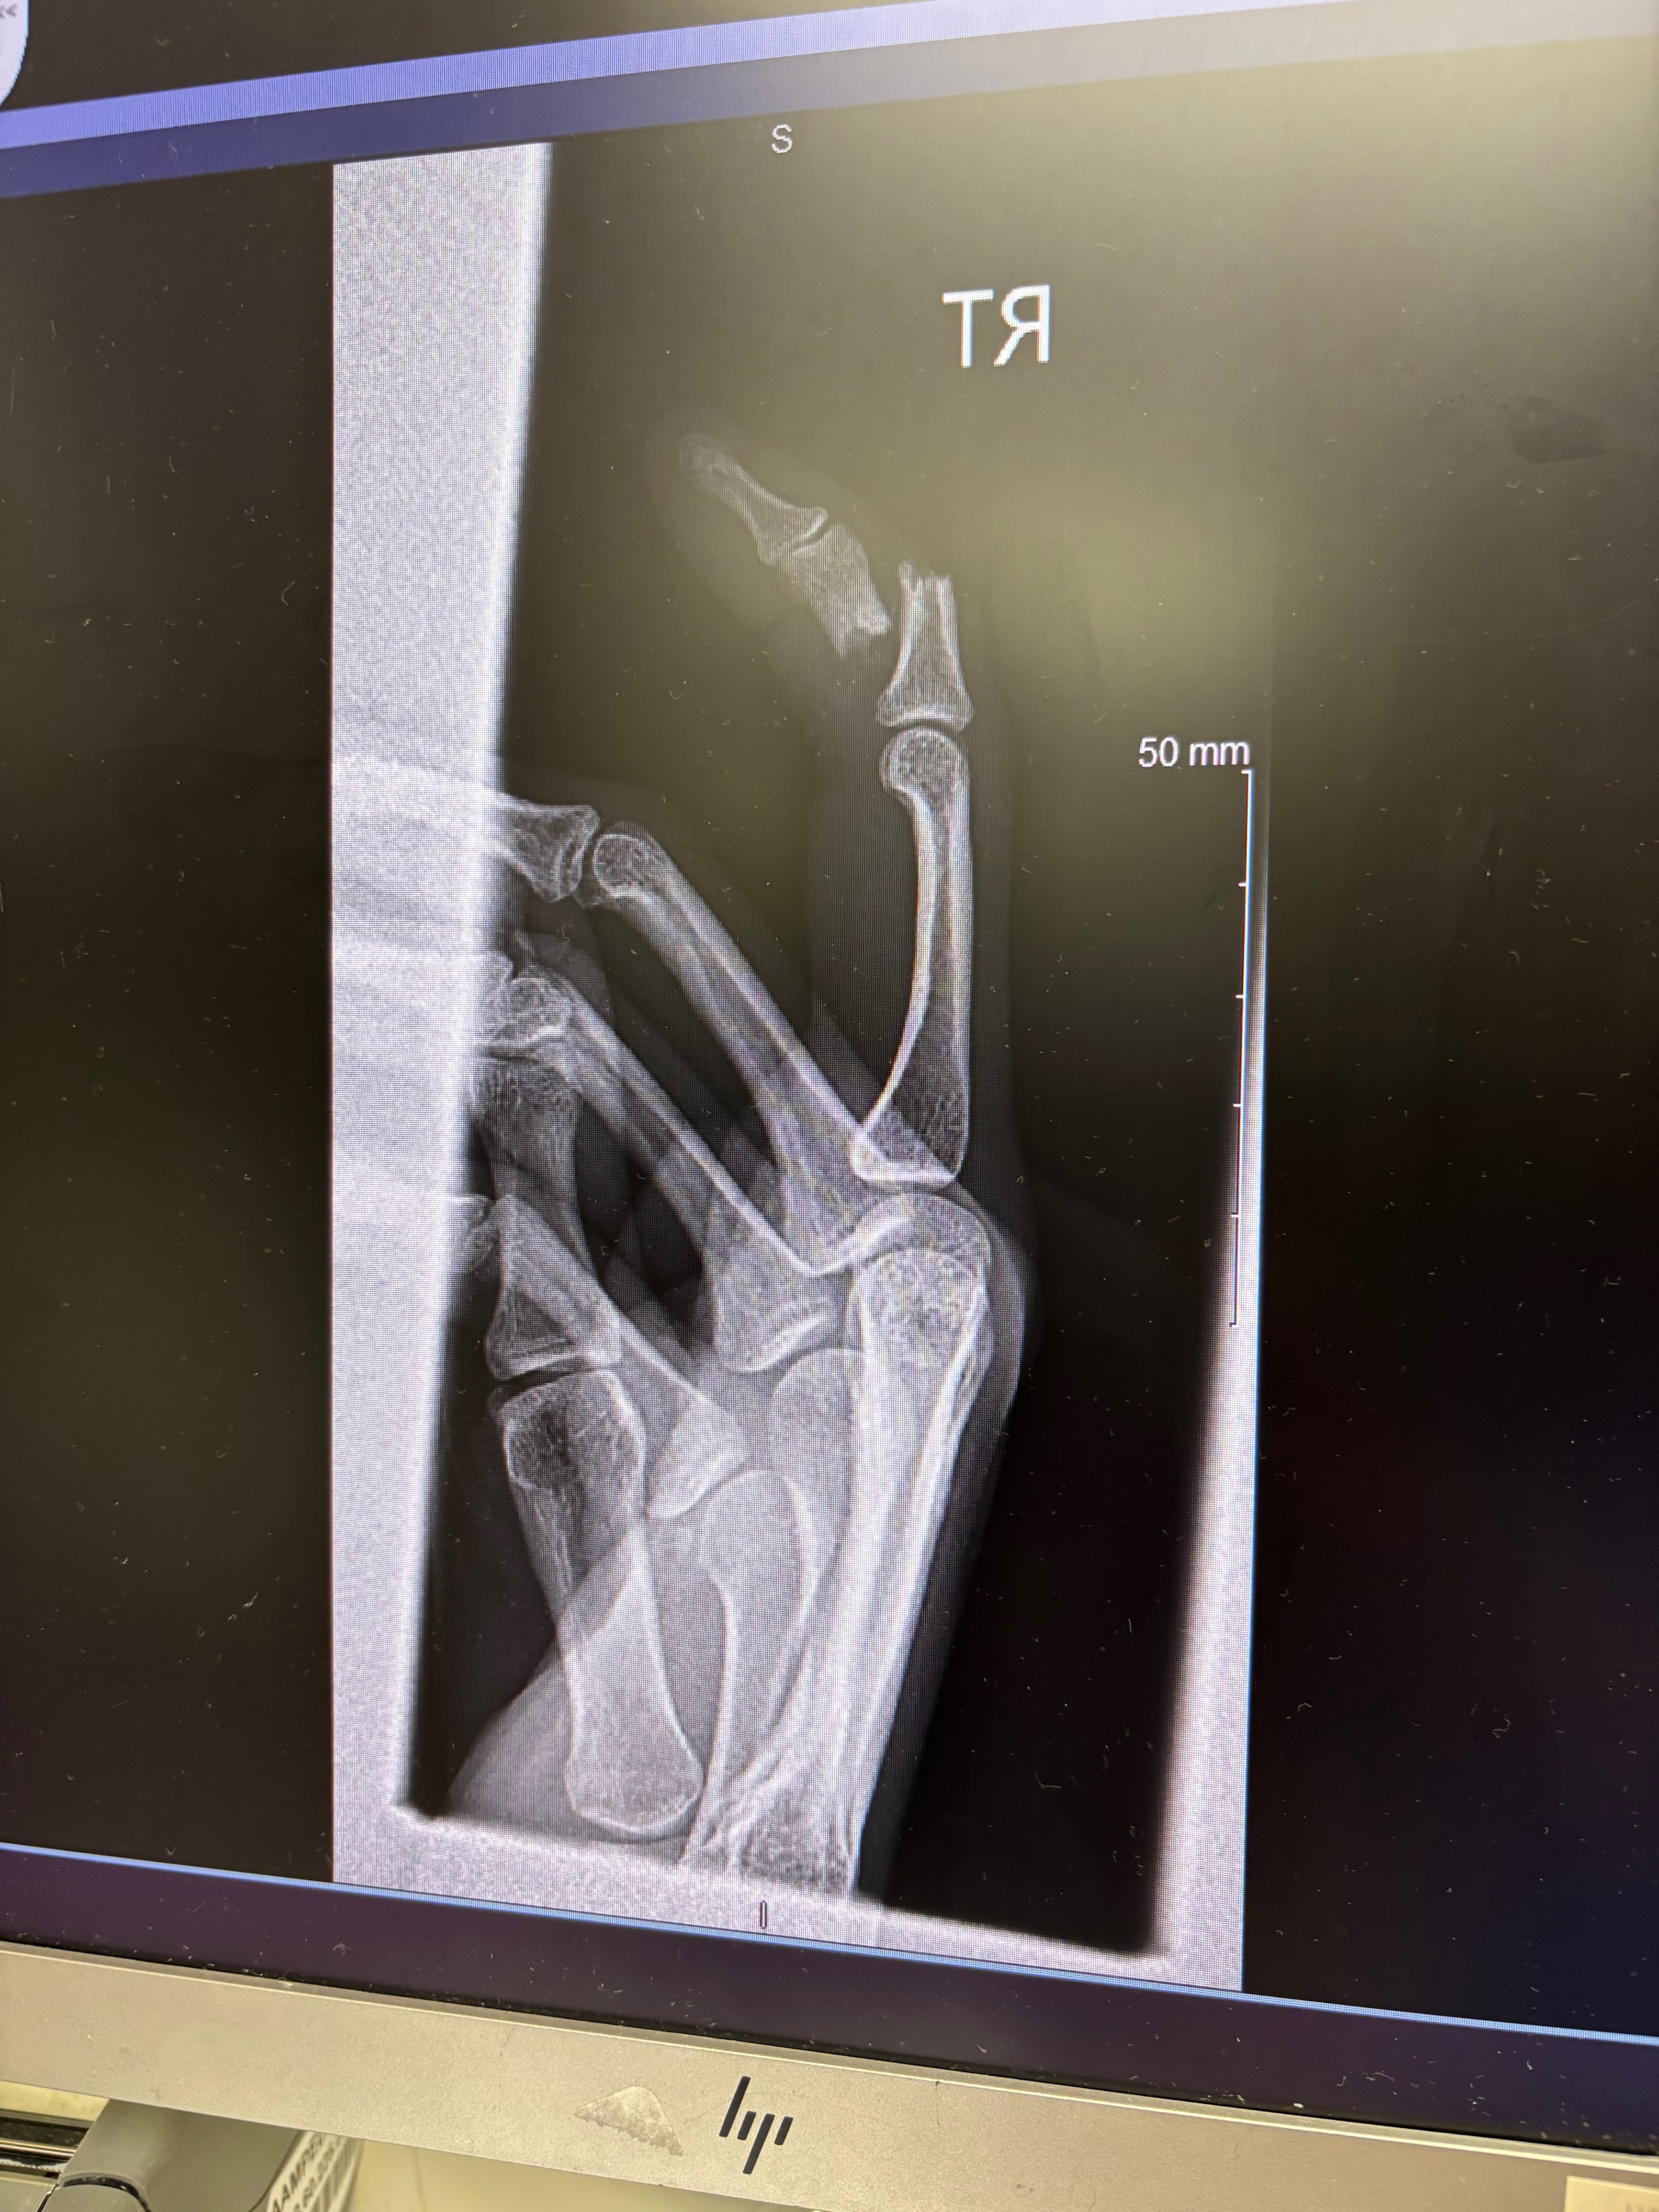

Cadence's arms and hands were severely damaged in an accident involving dogs. Arteries, tendons, and ligaments were severely damaged. She will be out of work for 3 months, needing long-term care and leaving her unable to work. Her employer has informed her that she will more than likely not have a job to come back to. She doesn’t want to get evicted or have her newly purchased car repossessed. I honestly feel odd asking for help, but I still cannot find full-time work to financially support her either. Any little bit will honestly help. I don’t even want to look at the hospital bill when it arrives.